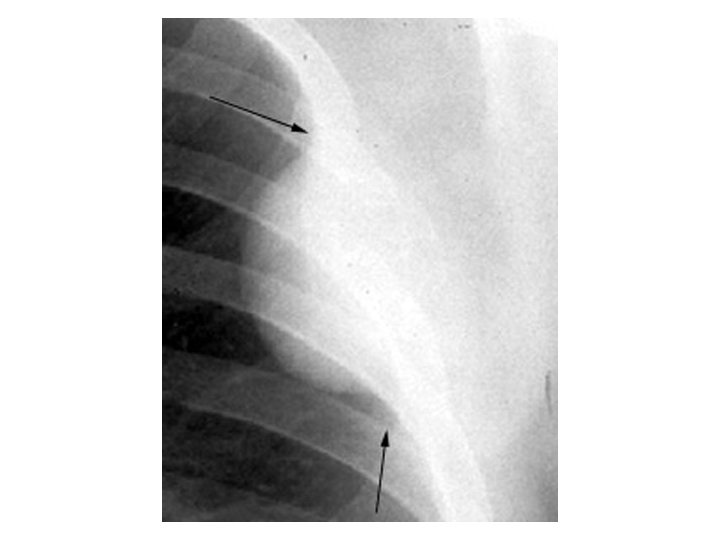

Extrapleural sign

Peripheral Sharp inner Indistinct outer Concave angles Extrapleural sign